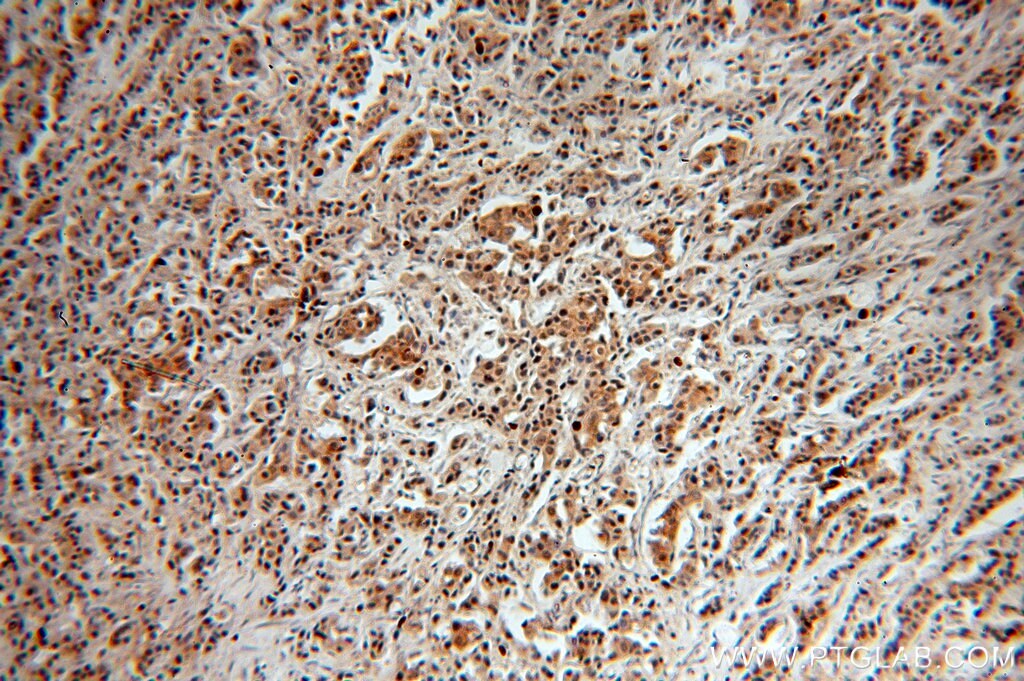

Supportive validation

- Submitted by

- Invitrogen Antibodies (provider)

- Main image

- Experimental details

- Immunohistochemistry of paraffin-embedded human breast cancer using 17707-1-AP (USP28 antibody) at dilution of 1:50 (under 10x lens).